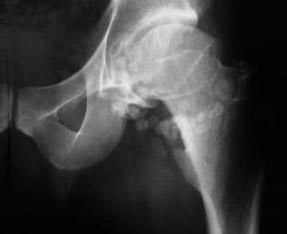

常繼發性的紅細胞增多症發生。腎細胞瘤常轉移肺骨肝等還存在不少非泌尿系統的腎外表現如高熱肝功能異常貧血高血壓紅細胞增多症和高鈣血症等最嚴重的併發症是死亡。